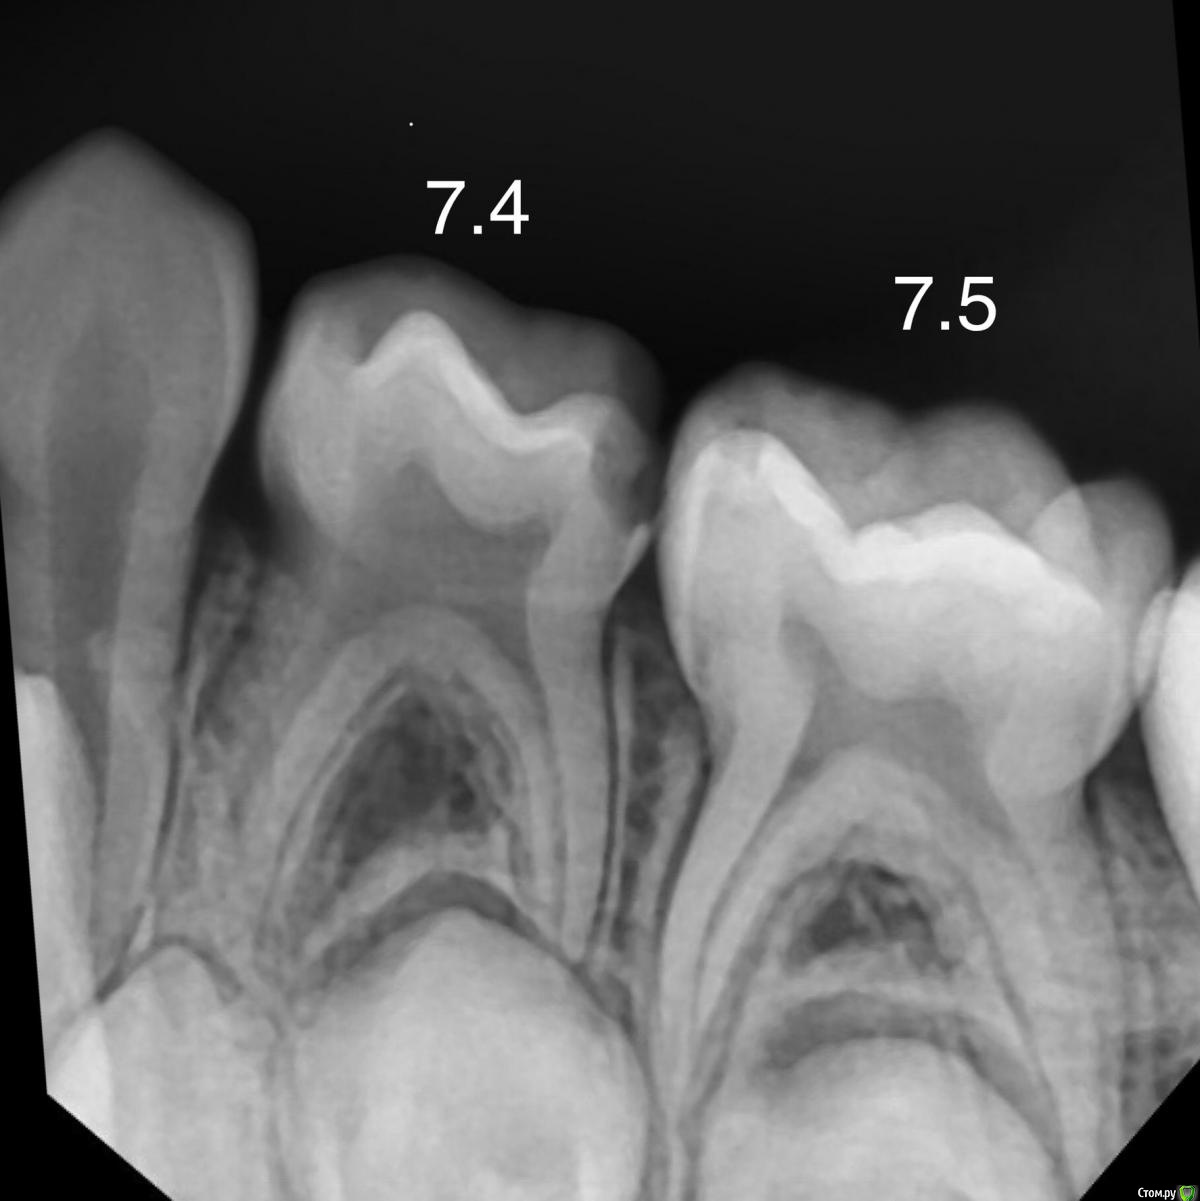

CRAZYDUCK Опубликовано 3 мая, 2018 Автор Поделиться Опубликовано 3 мая, 2018 Просто кариесули 7.4 и 7.5Обязательно убираем миловидную эмаль по контактам ( красной стрелкой на 7.5 указала )Обратите внимание , что rvg практически не визуализирует кариес медиально на 7.5 6 Ссылка на комментарий